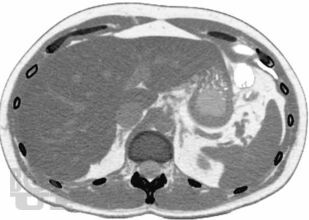

В руководстве подробно описана методология проведения компьютерно-томографического исследования при эндокринологических заболеваниях, рассмотрены основные диагностические аспекты и возможности компьютерной томографии при образованиях надпочечников, щитовидных и паращитовидных желез, гипофиза, заболеваниях костей и офтальмопатии. Продемонстрированы также возможности современной мультиспиральной компьютерной томографии в диагностике эндокринопатий. Издание иллюстрировано большим количеством компьютерных томограмм.